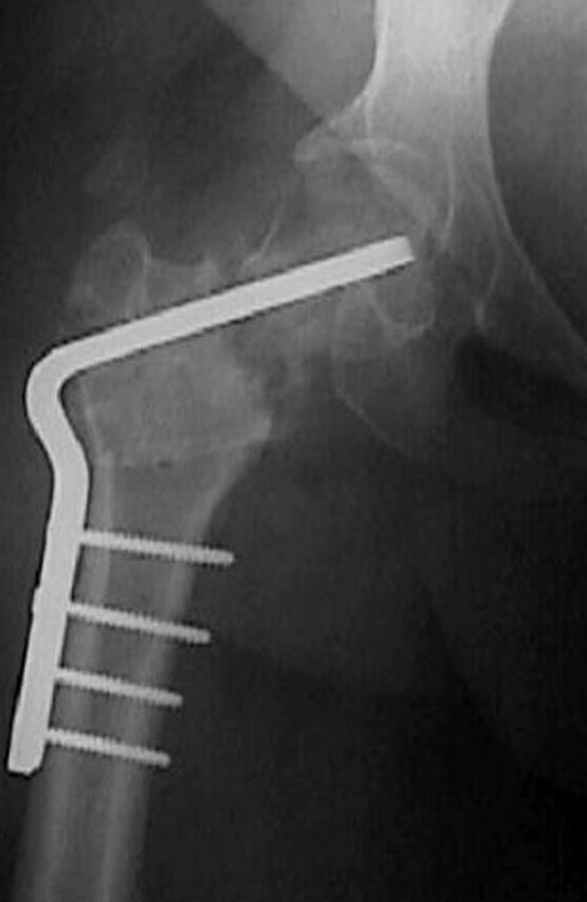

Если, например, доводится лечить больных с псевдартрозами шейки бедра, то надобность есть, и приходится. См. приложение.

Несколько снимков из моей коллекции, чтобы разьяснить, почему мы до сих пор делаем различные варианты остеотомии.

На рисунке N1 предоперационный план лечения ложного сустава шейки бедра- линия ложного сустава, угол и направление введения импланта, клиновидная остеотомия в градусах и миллиметрах, второй снимок после коррекции, расчет, на сколько удлиняется конечность и размеры импланта;

N3 рисунок окончательный снимок, после операции моя рентгенограмма должен выглядеть примерно как эта картина. На N4 снимке клин перед удалением; N5 послеоперации 3 нед.; N6 окончательная рентгенограмма.

варус при проксимальном отделе 95 градусной пластиной.